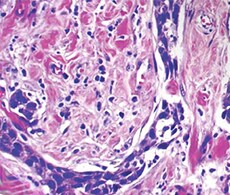

肿瘤活检的异质性导致难以使用全组织样本来生成有用的基因组数据。激光捕获显微切割 (LCM) 是一种强大的技术,有助于研究人员比较肿瘤组织与周围非肿瘤细胞的分子谱图,从而显示出个体患者肿瘤样本隐藏的分子特征,并引领定制治疗和个性化医学的发展。Arcturus LCM 系统的温和红外激光可保留已捕获细胞和相邻细胞的组织形态和遗传内容物,为研究人员提供了一种有效的工具,用于轻松确证捕获的材料,同时保持生物分子的完整性。